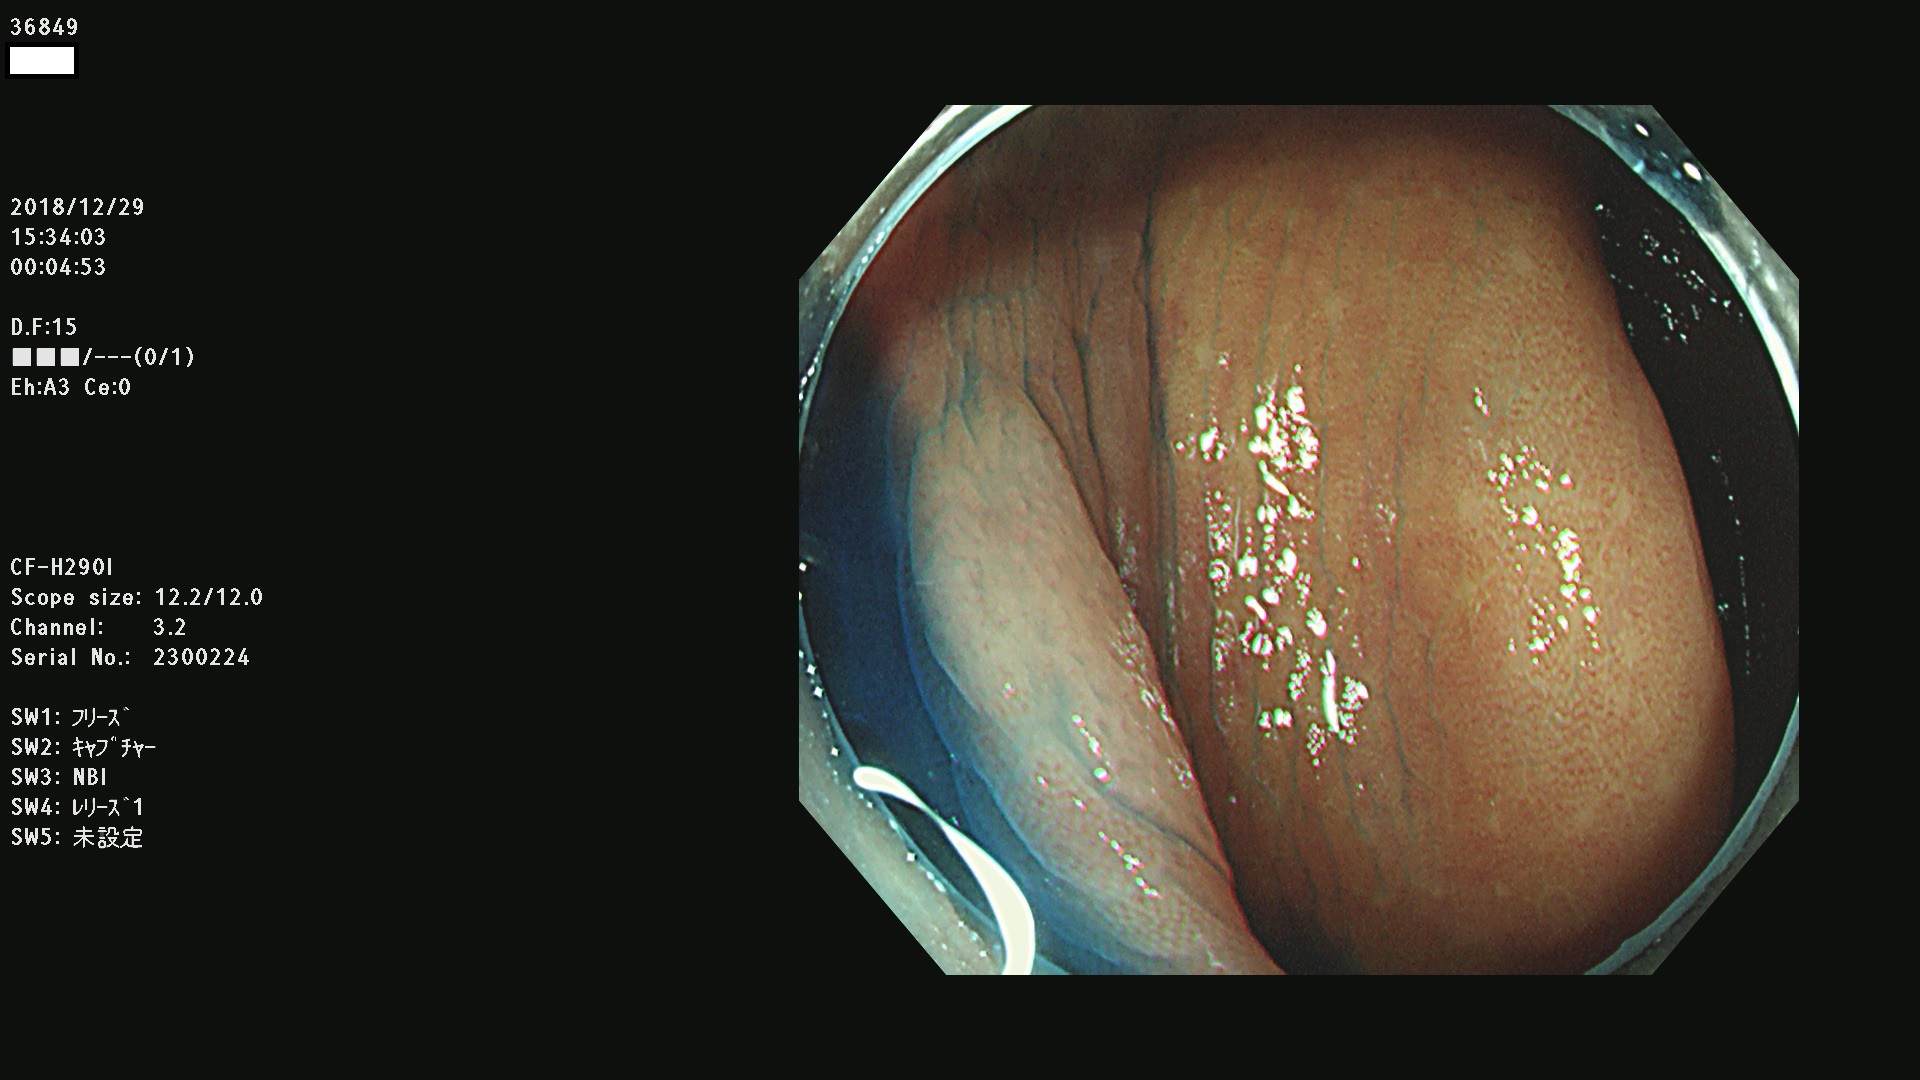

36804 36806 36807 36808 36809 36810 36811 36813 36815 36816 36817 36818 36820 36821 36822 36824 36825 36826 36828 36829 36830 36831 36832 36833 36834 36835 36837 36840 36841 36842 36845 36846 36848 36849 36851 36852 36853 36854 36855 36857 36859 36860 36861 36862(SSAPのみ) 36863 36864 36866 36868 36869 36870 36873 36875 36877 36878 36879 36881 36882 36883 36884 36885 36886 36887 36888 36889 36891 36892 36893 36894 36895 36896 36897 36898 36899

発見困難で危険性の高い平坦型病変(上記100名より抽出)